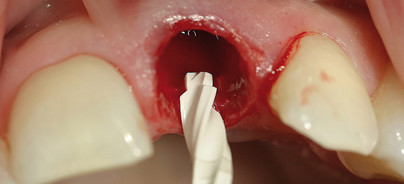

Bei einer 32-jährigen Patientin war eine Längsfraktur, ein Lockerungsgrad II sowie eine Verfärbung des Zahnes 21 zu beobachten. Nach der anamnestischen Befragung stellte sich heraus, dass der Zahn im achten Lebensjahr aufgrund eines Traumatas komplett luxiert wurde. Dieser wurde durch die damals behandelnden Zahnärzte wieder reponiert. Des Weiteren war auf der Panoramaschichtaufnahme eine endodontische Behandlung des Zahnes 21 zu beobachten. Die Taschentiefen waren mit 2 bis 3 Millimeter unauffällig ­sowie BOP-negativ. Auffällig ist, dass die gesamte Oberkieferfront verkürzte Zahnwurzeln aufweist, die mit hoher Wahrscheinlichkeit auf das Traumata zurückzuführen sind. Aufgrund der ästhetischen Bedürfnisse der Patientin, welche sich durch ihren Beruf erklären lassen, war es für sie wichtig, eine schnelle und optimale Lösung zu finden, um den Zahn 21 zu ersetzen. Ihr Wunsch war eine Sofortimplantation. Nach sorgfältiger röntgenologischer und klinischer Diagnostik konnte der Wunsch der Patientin berücksichtigt werden, was in diesem Fall zudem eine optimale Lösung bot. Mithilfe des DVTs wurde präoperativ die Implantation visuell simuliert und somit die Implantatlänge sowie der Durchmesser bestimmt. Die Extraktion wurde mithilfe der Piezochirurgie durchgeführt, um eine möglichst atraumatische Extraktion durchzuführen. Auf diese Weise konnten das Knochenfach sowie das Weichgewebe geschont werden und die so wichtige vestibuläre Knochenlamelle erhalten bleiben. Nach der Extraktion wurde das Knochenfach kontrolliert und zudem gründlich kürettiert. Um eine zusätzliche Keimfreiheit zu schaffen, wurde die Region mit einem CO2-Laser behandelt.

Für eine gute Primärstabilität wurde eine Bohrung nach apikal über das bestehende Knochenfach hinaus durchgeführt. Danach wurde das Implantat inseriert (Nobel Biocare Replace Select Tapered TiU RP 4,3x16). Zusätzlich wurde der Spalt zwischen Implantat und Knochen mit einem Gemisch aus Eigenknochen und Knochenersatzmaterial aufgefüllt. Anschließend erfolgte das Einschrauben eines Zirkonpfostens. Am Gingivalsaum wurde ein Verschluss mittels Opaldam und CO2-Laser durchgeführt. Mit speziellen Keramikschleifern wurde der Zirkonpfosten zurechtgeschliffen und anschließend das Provisorium angepasst. Um eine Reizung der Gingiva bzw. des OP-Gebiets auszuschließen, wurde das Provisorium kürzer gestaltet. Zudem ist es von großer Bedeutung, dass das Provisorium sowohl in der habituellen Okklusion als auch bei exzentrischen Bewegungen außer Kontakt geschliffen wird. Postoperativ gab es keine Komplikationen. Die Patientin hatte keinerlei Beschwerden. Eine Schwellung oder eine Entzündung waren ebenfalls nicht zu beobachten. Der Abdruck wurde nach vier Monaten mit einem individuellen Löffel genommen. Bei Frontzahnversorgungen ist es von großem Vorteil, wenn ein Zahntechniker im Hause zur Verfügung steht, um die Zahnfarbe direkt am Patienten zu bestimmen. Auf diese Weise kann der ästhetische Anspruch des Patienten im Frontzahnbereich optimal berücksichtigt werden. In diesem Fall wurde ein Wax-up hergestellt und ein Zirkonkäppchen mittels des CAD/CAM-Systems von NobelProcera gescannt. Anschließend wurde eine auf den Patienten genormte charakteristische Farbschichtung durchgeführt. Für ein optimales Ergebnis wurde die Krone mit einer Try-In-Paste anprobiert und anschließend adhäsiv eingesetzt.